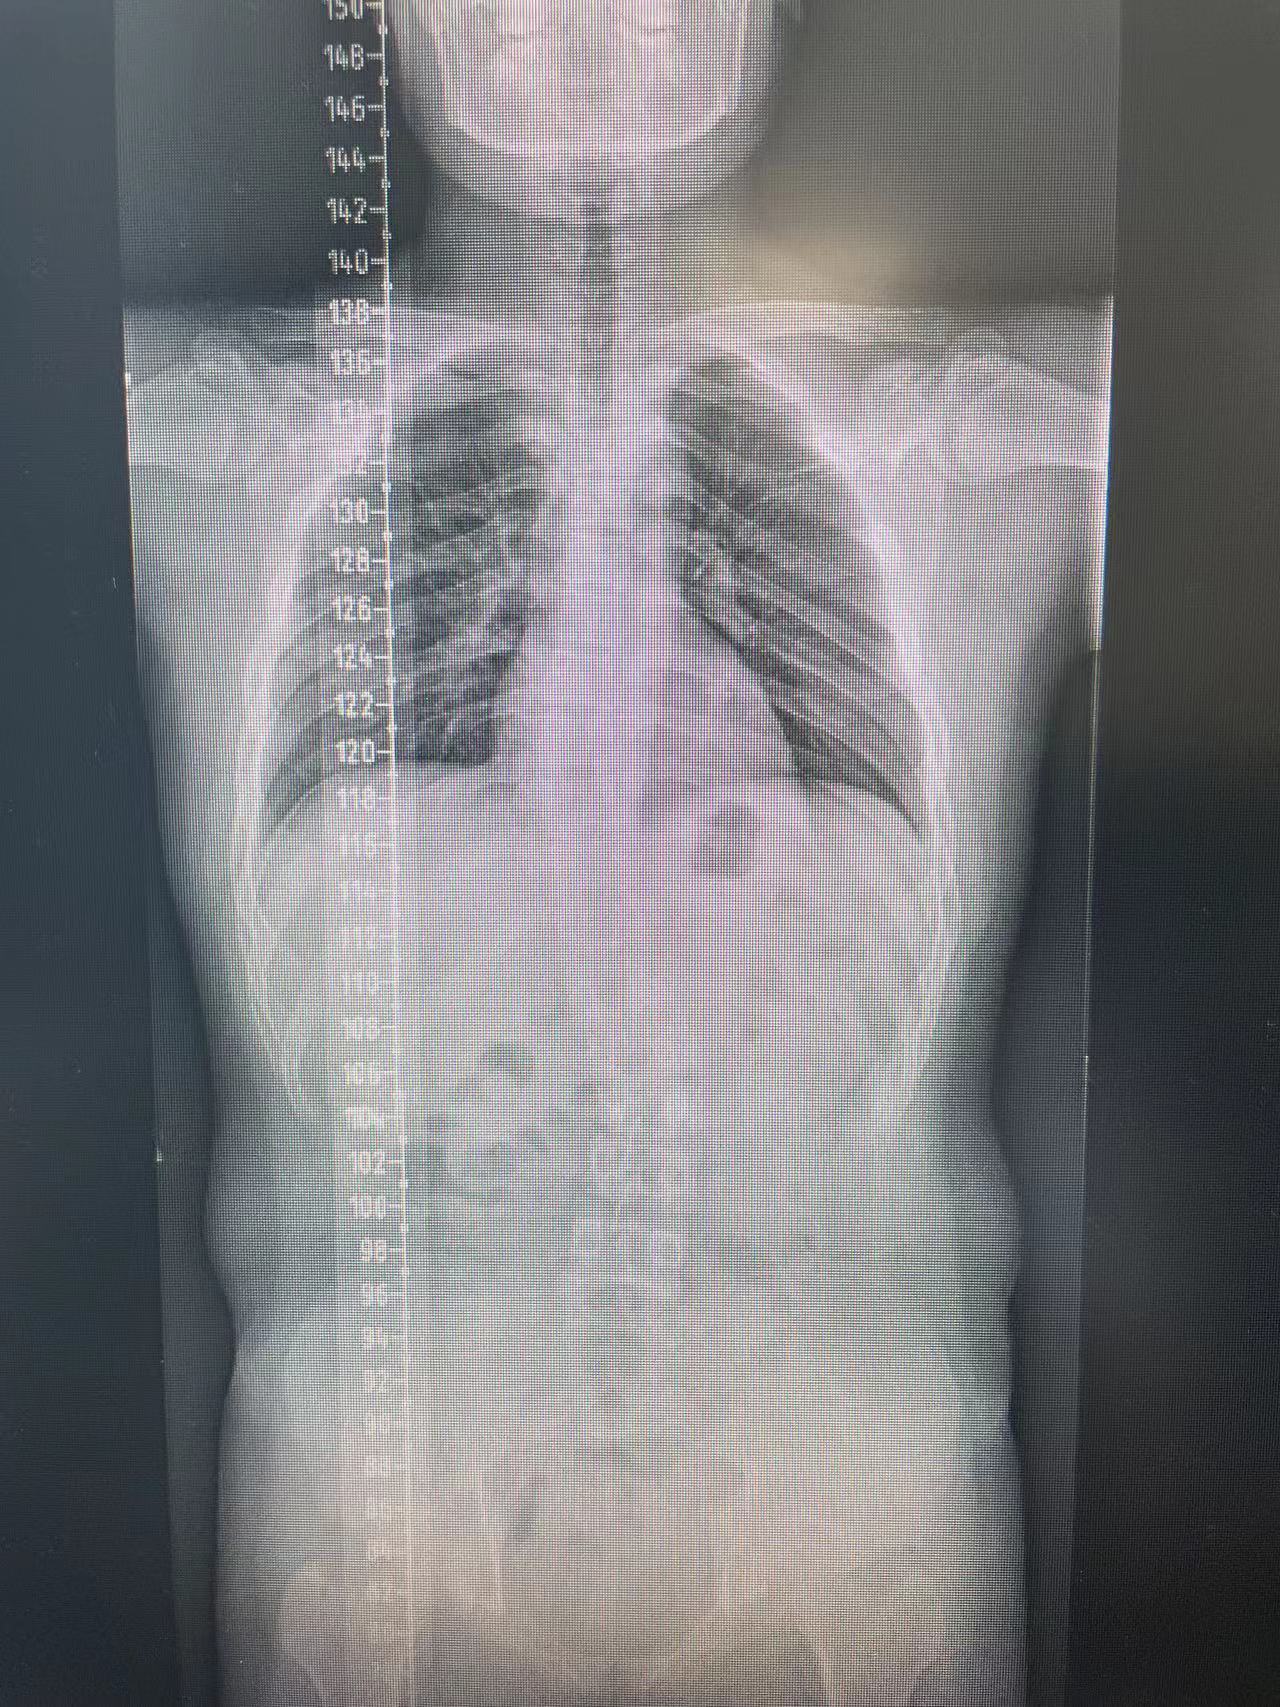

患者杨某,15岁,一年前在家中行走不稳,未及时给予系统治疗,现双下肢僵硬、无力症状明显,影响正常生活,遂前来我院脊柱外科中心D区接受住院治疗。

脊柱外科中心D区辛大奇、王东海、孙洪岩医疗团队完善患者术前检查后,明确诊断为胸12半椎体侧后凸畸形,经过积极与胡侦明教授沟通、讨论后,共同为患者制定手术方案,为患者施行先天性脊柱侧弯、半椎体侧后凸畸形截骨矫形+植骨融合内固定术。